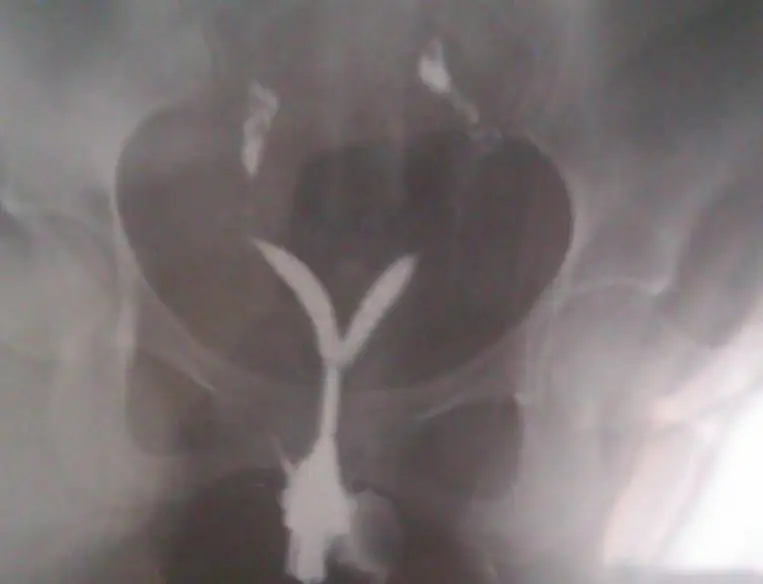

merhaba arkadaşlar.ben aranıza yeni katıldım. ben 2,5 yıllık evliyim. 2 yıldır bebek istiyorduk ve sonunda geçen ay hamile kaldım fakat 5 haftalık bir gebelik sonucu düşük yaşadım malesef. doktor muayenede rahimimim çift olduğunu ve rahimde perde olduğunu ayrıca rahimimin ters olduğunu söyledi.ve rahim filmi istedi.bu hafta rahim filmini çektirdik.fakat rahim emarı da istiyor doktorum onu da haftaya çektireceğim. şimdi resimlerini yüklüyorum rahim filmimin.sizce rahimde perde mi var yoksa rahim çift mi ? internetten araştırdım şekline bakılırsa ''Uterus bicornis'' gibi geliyor bana. daha doktorum bieşy demedi.emarı da görüp öyle söyleyecekmiş.sizce nedir? çift rahim mi yoksa rahimde perde mi ????

sağol canım teşekkür ederim.tüpler açıkmış şükürler olsun . ama işte o Y harfi gibi görünen perde mi yoksa çift rahim mi işte o çok önemli benim için. inş perdedir diyorum dua ediyorum artık. perde ise çözüm kolay çünkü.ufak bir operasyonla perdeyi alabiliyorlarmiş.

emar sonuçlarımı da dün aldım. malesef ki çift rahim dedi doktorum. histereskopi ye gerek yok emar da gayet belli dedi. uterus bicornis imiş benim durumum. yani tek giriş ama sonradan ikiye ayrılıyo Y gibi aynen. ve ameliyat pek yapılmıyormuş bu duruma. doktorum da zaten kesinlikle ameliyat önermiyorum dedi. tek yapacağımız hamile kaldığında düşük olmaması için elimizden geleni yapmak dedi. böyle işte. malesef üzgünüm.çünkü düşük ihtimalim çok çok yüksek olacak.

arkadaşım öncelikle geçmiş olsun diyorum. ve kendi yaşadıklarımdan yola çıkarak sana başka doktorlara da gitmeni tavsiye ediyorum.bende 29 yaşındayım. yaklaşık 2 yıl önce bebek düşünmeye başladığımızda önce doktora gittim.tabi eşimde gitti sperm tahlili filan yaptırdı.bende bir rahatsızlığım varsa önce tedavi olayım ki vakit kaybetmeyeyim dedim. gittim muayene oldum tahlil filan verdim. doktor bana hiçbir şeyin yok herşeyin normal , stres yapma zamanla hamile kalırsın dedi. bende 2 yıl bekledim herşeyim normalde stresten olmuyo herhalde dedim.geçen ay hamile kaldım ve hamile olduğumu öğrendikten 1 hafta sonra yani 5 haftalık iken gebeliğim düşükle sona erdi. bu sefer kardeşiminde gittiği doktora gideyim dedim. doktor ilk muayene de o an söyledi . sende ya çift rahim var yada rahimde perde var dedi. hemen rahim filmi yani HSG istedi. o hafta rahim filmi çekildim. gene tam net anlaşılmadı bu sefer rahim emarı istedi doktorum. çünkü histereskopi biraz daha zor bişey dedi.şimdi boşu boşuna delik açmayalım göbeğine dedi. emar da sonuçsuz kalırsa son çare histereskopi yaparız dedi. bir de histereskopi pahalı da bişey. boşuna dünyanın parasını verme dedi.neyse rahim emarı da çekildim. sonuç olarak çift rahim çıktı. benimkinin ismi ''uterus bicornis'' yani çift boynuzlu rahim. benim tüpler açıkmış yumurtalar normalmiş fakat işte çift rahim.aynı Y harfi gibi görünüyor rahim filminde. hatta fotosunu bir iki sayfa öncesine yüklemiştim bakabilirsin. yani diyeceğim o ki ; bir doktor yüzünden tam 2 yıl kaybettim. herşeyim normal sandım. meğerse hiç de öyle değilmiş. tek doktorla kalma konusunda çok iyi doktorlara git derim. yaş da 29 olunca fazla vakit kaybetmemek gerekiyor mecburen. benim doktorum bana hamile kalabileceğimi ve doğum yapabileceğimi söyledi.normal hamilelerden tek farkın ilk 3 ay düşük riskin yüksek olacak ve yatmak zorunda kalabilirsin dedi.3.cü ayında rahimine dikiş atarız böylece erken doğumu engellemeye çalışırız dedi. normal rahimlilere göre rahimin yarım sayılır fakat millet ikiz doğuruyor sende tek doğurursun nolcak yani bişey olmaz dedi. tabi ben aynı film ve emar sonuçlarını uzman başka doktorlara da götürdüm onlarda aynı teşhisi koydu. bence önce bir emar çektir derim. hiç olmazsa histereskopi yapılır. biraz uzun yazdım k.bakma lüften.